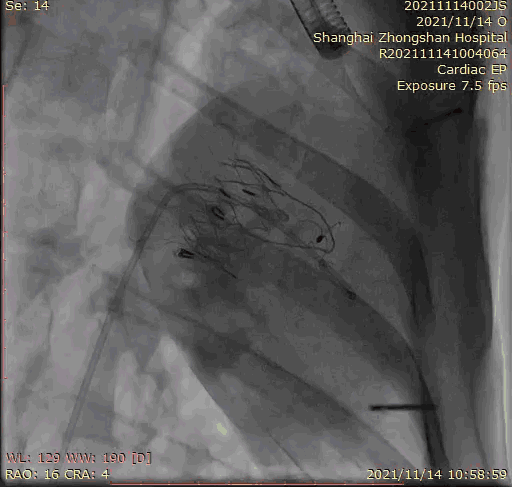

上海中山醫(yī)院葛均波院士、錢菊英院長、周達新教授、潘文志教授、潘翠珍教授、李偉教授共同完成此次臨床前研究。術后葛均波院士對Lux-Valve Plus的器械操作性能給予了高度評價,DSA和超聲影像也顯示出在本次研究中Lux-Valve Plus的安全性和有效性俱佳。

本次臨床前研究經(jīng)右側頸靜脈置入LuX-Valve Plus輸送系統(tǒng)可調彎鞘管,在DSA及超聲引導下將人工三尖瓣瓣膜植入到原有三尖瓣位置,利用獨特的錨定技術將人工瓣膜支架可靠固定在預定的位置。